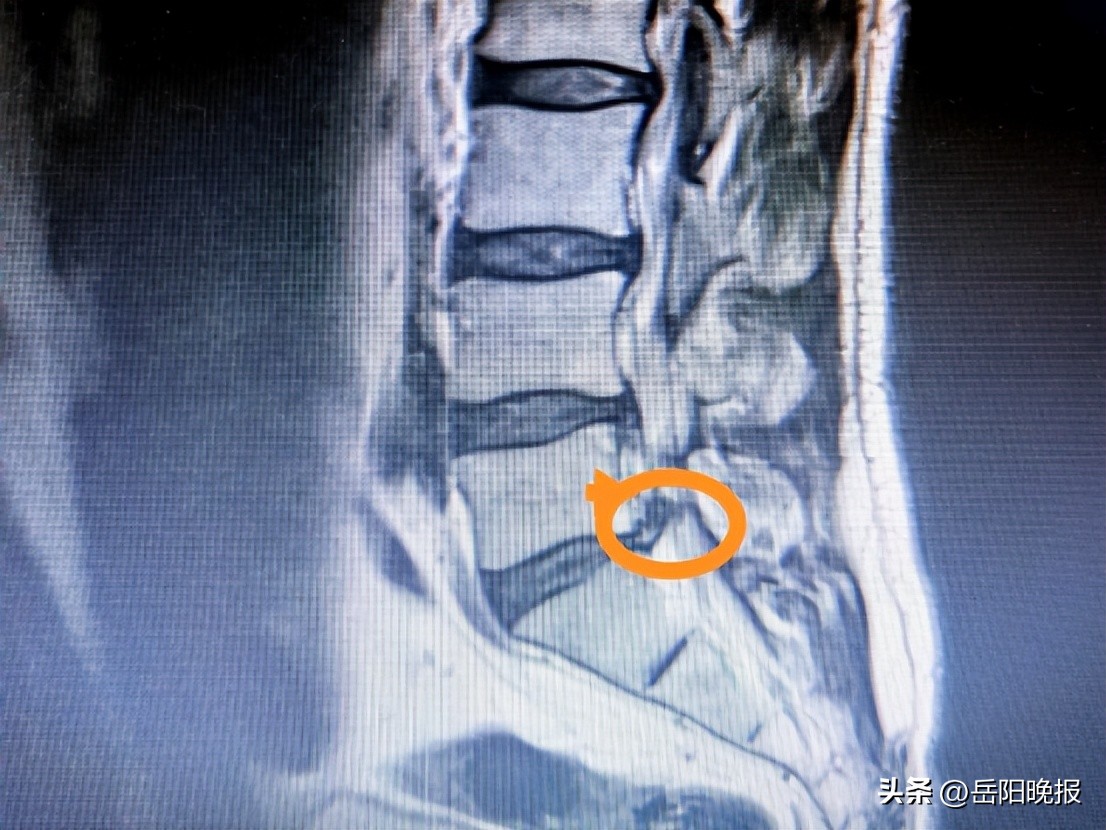

尚主任了解毛大哥的病情后,对其进行了详细的身体检查。检查结果显示,毛大哥腰肌非常紧张,第三、四、五腰椎右侧有较明显的压痛感,并在屈颈试验时出现阳性反应,右下肢直腿抬高试验也呈阳性反应。此外,他的右脚拇指背伸肌力量减弱,但肌肉没有明显萎缩,“4”字征呈阴性。腰椎MRI检查结果显示,毛大哥的L5/S1椎间盘脱出,导致右侧神经根受到压迫。